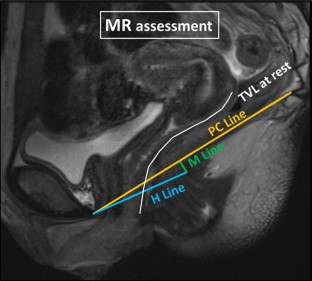

Fig. 2